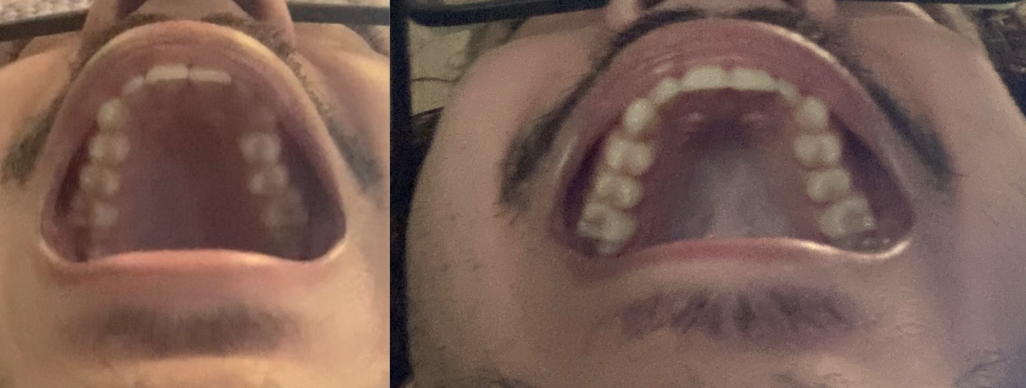

Before and after about 3 months apart, but I had most of the change in the second month anyway

BEFORE AFTER

I tried to crop the images but now it seems like I zoomed in and fraud the results, if anyone has doubts I could respond with the uncropped version of the images IDC

OFC I didn't expect any skeletal change I only wanted to fix my occlusion because my midline was fine but had some teeth flared inwards and some outwards, resulting in a fcked up occlusion also you can see how overcrowded af my lower arch is

Before and after about 3 months apart, but I had most of the change in the second month anyway

BEFORE AFTER

I tried to crop the images but now it seems like I zoomed in and fraud the results, if anyone has doubts I could respond with the uncropped version of the images IDC

OFC I didn't expect any skeletal change I only wanted to fix my occlusion because my midline was fine but had some teeth flared inwards and some outwards, resulting in a fcked up occlusion also you can see how overcrowded af my lower arch is